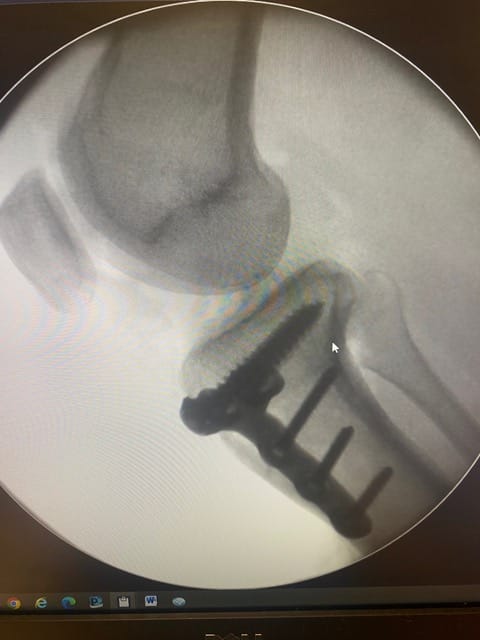

Bodycad has transformed the accuracy and success of this operation. It offers 3D analysis of the patient’s pre-op situation, patient-specific instrument and plate design, 3D printed bone models, personalized surgical guides, and personalized plate solutions. This patient specific design leads to better accuracy and outcomes.

In this case, a young patient had knee pain due to deformity in the tibia. This occurred secondary to a fracture that had disturbed their growth plates as a child. The accuracy of the correction that BC Fine Osteotomy achieved is fantastic and should allow a return to pain free function.